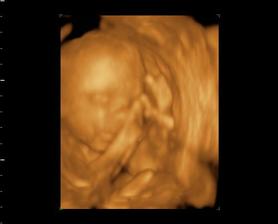

Naša Emilly

Zaciname 39tt, termin mame 23.10.09, uvidime, kedy sa malej bude chciet ist na svet a vidiet svojich rodicov. Sice sme mali neplanovane tehotenstvo, ale o to viac nas to potesilo a na malu sa nesmierne obaja tesime..je to u nas prve vnucatko, tak to bude lasky a lasky, ale tej dame aj druhemu aj tretiemu babu, uvidime, kolko nam ich zivot da. I ked mamina este studuje, urcite to zvladneme..